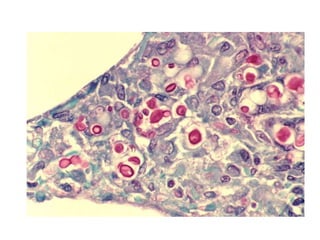

• #28  Densely matted pseudohyphae and budding spores in squamous debris, fibrinopurulent exudate or necrotic debris Underlying active esophagitis HIV patients may have invasion into muscularis propria and adventitia if untreated (Mycoses 1997;40 Suppl 1:81)

• #29 PAS 40 x

Case 3 • 68year old male • C/O- Dysphagia , retrosternal pain since 2 days, was on treatment for UTI • O/E- Normal • On Endoscopy- Thick , curdy white patches on esophageal wall